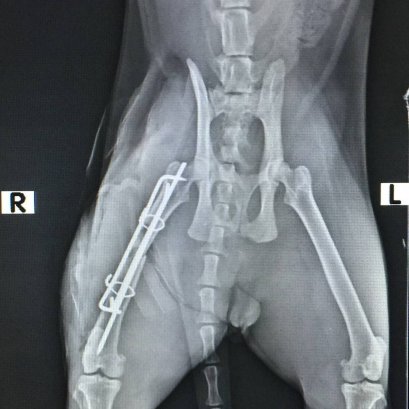

น้องเจี้ยบ ออกไปวิ่งเล่นนอกบ้าน กลับมาอีกทีก็เดินขาลากมาแล้วค่ะ น้องเจี้ยบมาพบคุณหมอด้วยอาการขาหลังขาขวาบวมและไม่สามารถยืนได้ปกติ หมอจึงรีบทำการตรวจวินิจฉัย ด้วยเครื่องเอ็กเรย์ดิจิตัล ก็พบว่ากระดูกท่อนบนของขาหลังข้างขวาหักออกเป็น 2 ท่อน เบื้องต้นจึงได้ทำการปฐมพยาบาลด้วยการให้แก้ปวดลดอักเสบ และพันเฝือกอ่อนเพื่อประคองขาข้างที่หักไว้ เพื่อไม่ให้มีการเคลื่อนไหวมาก จะได้ไม่อักเสบมากไปกว่าเดิม เพื่อรอทำการผ่าตัดแก้ไขภาวะกระดูกหักต่อไปค่ะ